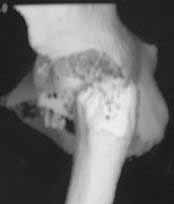

Male 22 yrs of age, RTA, front seat passenger in a truck. Sustained grade IIIB fracture of Tibia, and a Posterior dislocation of the Ipsilateral Left Hip.

Emergent closed reduction performed, and Tibial wound debrided. Next day Exfix applied and fibula plated. Initially femoral head fracture was not appreciated and it was thought that this is a posterior wall fracture. Presently two weeks down the line, Tibial wound is better but not completely healthy. and plastics want to wait for another five days, before they flap it. I enclose radiographs, Judet view, Ct scans in this and following mails.

Based on the selected images that you shared with us, I would not leave it as is. The fragment is significant in terms of its size and location and displacement.